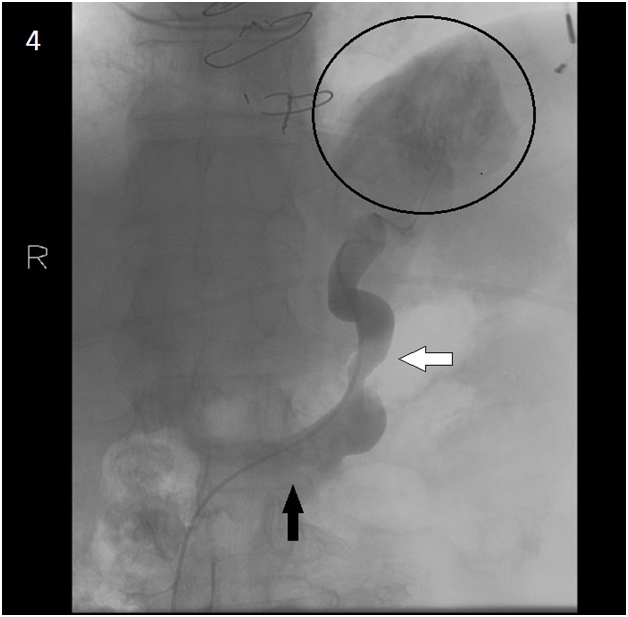

Giving the patient’s clinical history of severe heart failure and upper GI bleeding due to gastric varices, we presumed that the patient developed portal hypertension, secondary to cardiac cirrhosis. Since, endoscopic treatment of the varices was not feasible, the patient was planned for Transjugular Intrahepatic Portosystemic Shunt (TIPS) under general anesthesia. At the beginning of the procedure, the central venous and hepatic wedge pressures were accessed via right transjugular route. The pressure measurements were as following: central venous pressure was 25 and 27 mm Hg in right atrium and in inferior vena cava respectively. Hepatic vein wedge pressure, representing portal vein pressure, was 30 mm Hg, with measured Portosystemic Venous Gradient (PSVG) of 5 mm Hg. Due to extremely high central and right heart pressures, and absence of significant PSVG, the TIPS procedure was aborted. Then, we attempted direct embolization of the varices via spontaneous gastro-renal shunt. The right femoral vein was accessed and venography performed. To our surprise, we observed upward (hepatopetal) blood flow through the spontaneous shunt towards the gastric varices (Figures 4 & 5). The varices were successfully embolized via the shunt with resolution of patient’s bleeding. After successful embolization of gastric varices the patient stopped bleeding, and was eventually discharged home. Unfortunately he died three weeks later because of worsening end heart failure.

Figure 4 Venography. The catheter enters Inferior Vena Cava and passes to the shunt (transparent arrow) via the Left Renal Vein (solid arrow). The varices are outlined (circle).